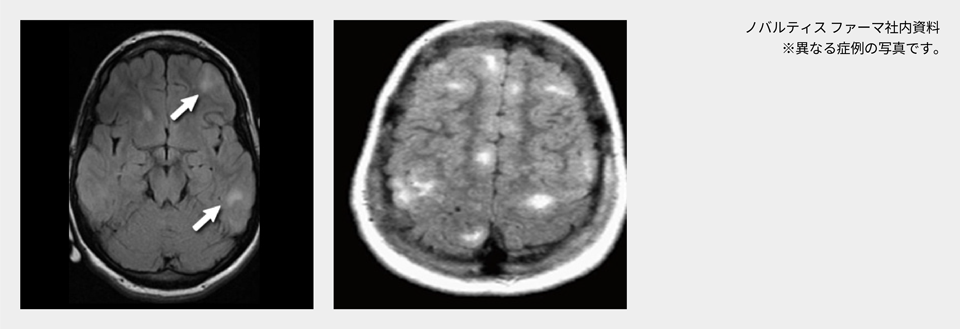

脳病変(SEGA、大脳皮質結節、SEN等)

結節性硬化症に伴う脳病変の種類

結節性硬化症患者の脳病変には、①上衣下巨細胞性星細胞腫(subependymal giant cell astrocytoma:SEGA)、②大脳皮質結節(cortical tuber)、③上衣下結節(subependymal nodule:SEN)、④放射状大脳白質神経細胞移動線があります(表1)1)~3)。

② 大脳皮質結節(cortical tuber)

大脳皮質結節は、本疾患の病名Tuberous Sclerosisの由来となった病変で、大脳皮質にできる直径1cm程度から5cm程度までの限局した結節性の病変です。

大脳皮質結節は、結節性硬化症の精神神経学的症状(てんかん、精神遅滞、自閉症など)と関与しており、結節数が多いほどてんかん発作をおこしやすく発達への影響が強いとされる報告もあります。